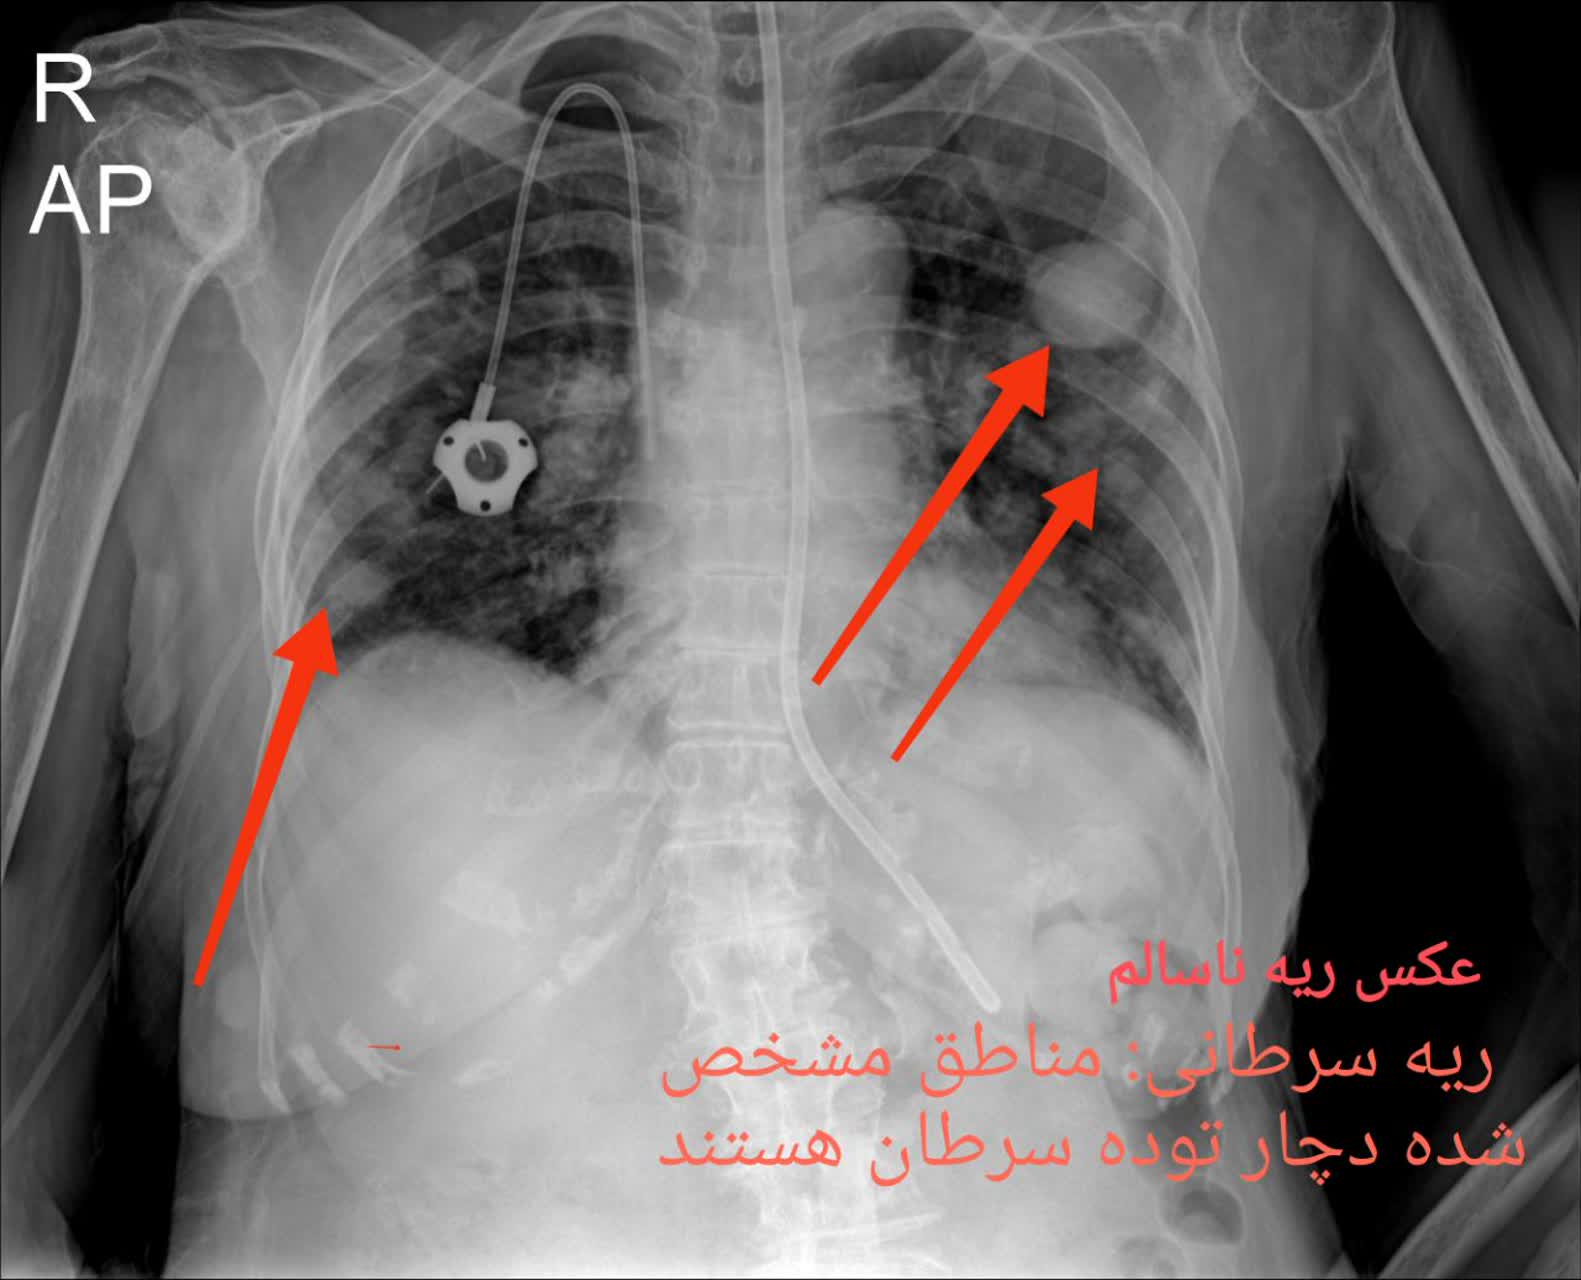

3. سرطان ریه: سرطان ریه یکی از بخشهای مهم سرطان است و ممکن است در افرادی که سیگار میکنند یا به عوامل ریسک دیگری تعریف شدهاند، پدیدار شود.

مقایسه عکس ریه سالم و ناسالم

در عکس ریه سالم و ناسالم، تفاوتها معمولاً با چشم غیرمسلح نیز مشهودند. ریه سالم تصویری یکنواخت و شفاف دارد، با خطوط ریوی طبیعی و بدون سایه یا توده. در مقابل، ریه ناسالم ممکن است سایههای غیرطبیعی، نواحی سفید شده (indicative of consolidation)، خطوط پررنگتر ناشی از فیبروز یا تودههای نامنظم را نمایش دهد. تشخیص این تفاوتها توسط پزشک رادیولوژیست، نیاز به تجربه و تجهیزات باکیفیت دارد، چیزی که در خدمات رادیولوژی ریه در منزل تهران و رادیولوژی ریه در منزل کرج فراهم شده است.